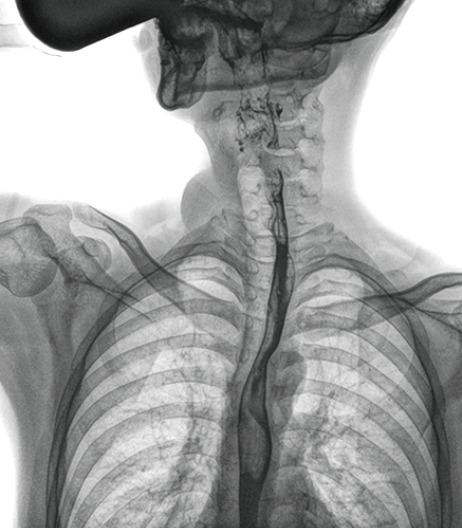

食管造影是食管病變的基本檢查方法,可以發(fā)現(xiàn)食管癌的特征性改變——食管粘膜的中斷和破壞,病人常感覺(jué)吞咽障礙,此特征在臨床中最常見(jiàn),也是早期食管癌的典型表現(xiàn)。一般伴隨的特征有管壁充盈缺損、龕影、軟組織塊影、食管腔狹窄等;在透視下還可看到食管壁僵硬、蠕動(dòng)緩慢等。

在食管造影檢查中,由于吞咽鋇劑后,造影劑流速非???,動(dòng)態(tài)DR影像采集幅面大,普利德多功能動(dòng)態(tài)DR 17×17英寸超大視野,一次曝光即可顯示整個(gè)食管,更方便觀察食管的病變,確定病變的范圍,對(duì)診斷和治療有重要參考價(jià)值。

動(dòng)態(tài) DR 可以動(dòng)態(tài)觀察管壁蠕動(dòng)是否僵硬,以鑒別良、惡性狹窄,不但在透視過(guò)程中,可實(shí)時(shí)高清點(diǎn)片,實(shí)現(xiàn)毫秒級(jí)動(dòng)靜態(tài)圖像切換,快速捕捉病變部位的影像,成像清晰而迅速,盡可能減少食管功能性障礙患者因吞咽困難而忍受痛苦的時(shí)間,同時(shí)提高醫(yī)生做出正確診斷的效率,還能實(shí)時(shí)保存視頻影像,反復(fù)觀察、分析,明確病變范圍,對(duì)手術(shù)有重要的指導(dǎo)意義。

與過(guò)去的數(shù)字胃腸機(jī)比較,動(dòng)態(tài)DR圖像分辨率高,對(duì)食管的全景觀察,局部粘膜破壞、中斷,管腔狹窄以及病灶范圍的顯示清晰度明顯更優(yōu)。

上消化道造影高清圖像